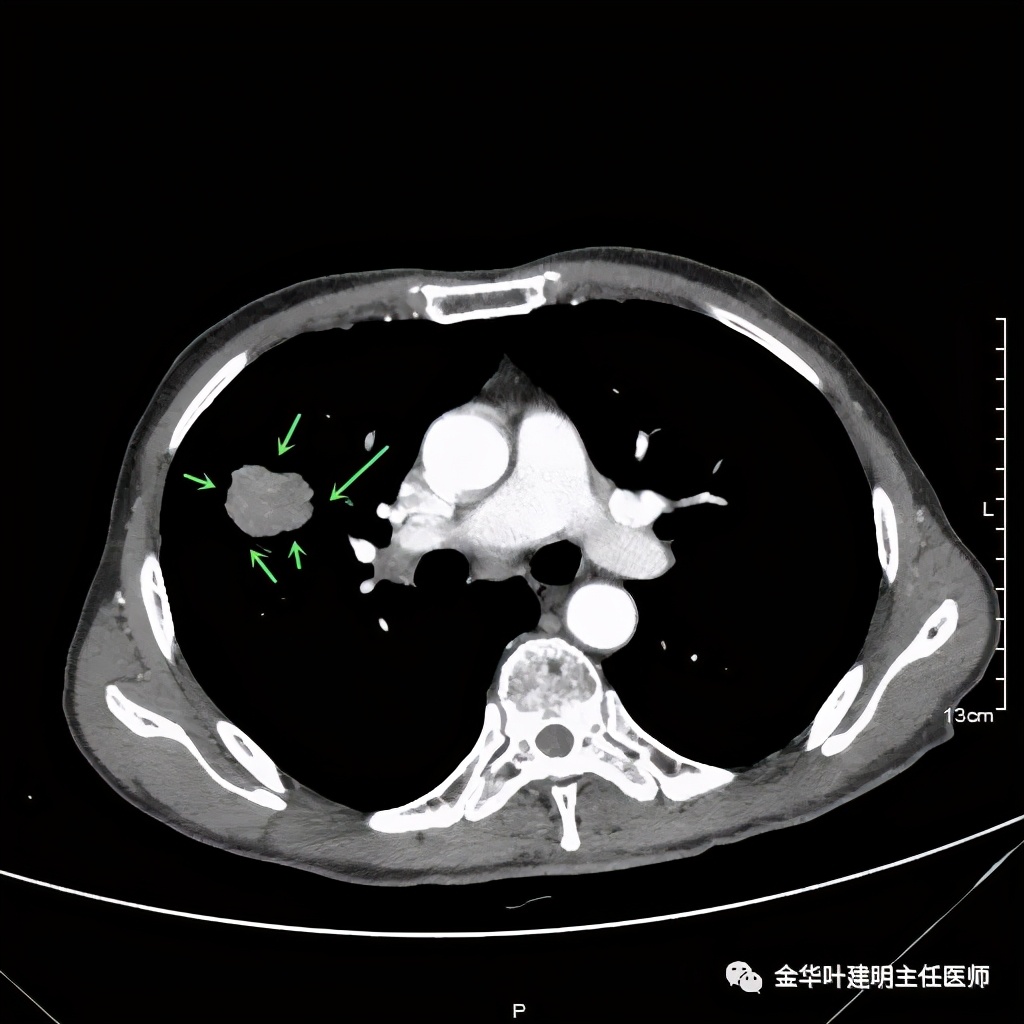

上图示纵隔窗实性

上图示纵隔窗密度不均

上图示纵隔窗病灶有膨胀性,内部有强化较明显的条索状(新生血管?)

上图示纵隔窗病灶表面欠平整,中间有小空洞,密度不均,局部似有坏死(空洞旁边)

上图示病灶快要消失的层面